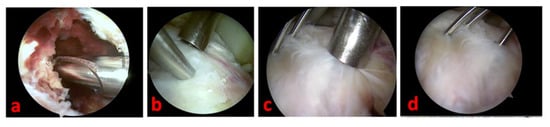

A complete radiographic knee series with AP, lateral, tunnel, and Merchant views is a major support. A true lateral view with the knee in hyperextension is useful in determining the reducibility of the fragment; it helps us, especially in the case of type II avulsions. The radiographic series can be integrated with a CT scan (to further delineate the fracture pattern: size, shape, fragmentation, and comminution) and MRI (to assess for associated intraarticular injuries) [10]—(Figure 1).

Figure 1.

A true lateral knee radiographic view of the right knee of a 16-year-old male patient of our series shows a Type 3 tibial avulsion fracture (a); CT scans are useful to define the pattern of the fracture and drive the management: CT sagittal view scan (b) and 3D CT reconstruction (c) of the same patient.